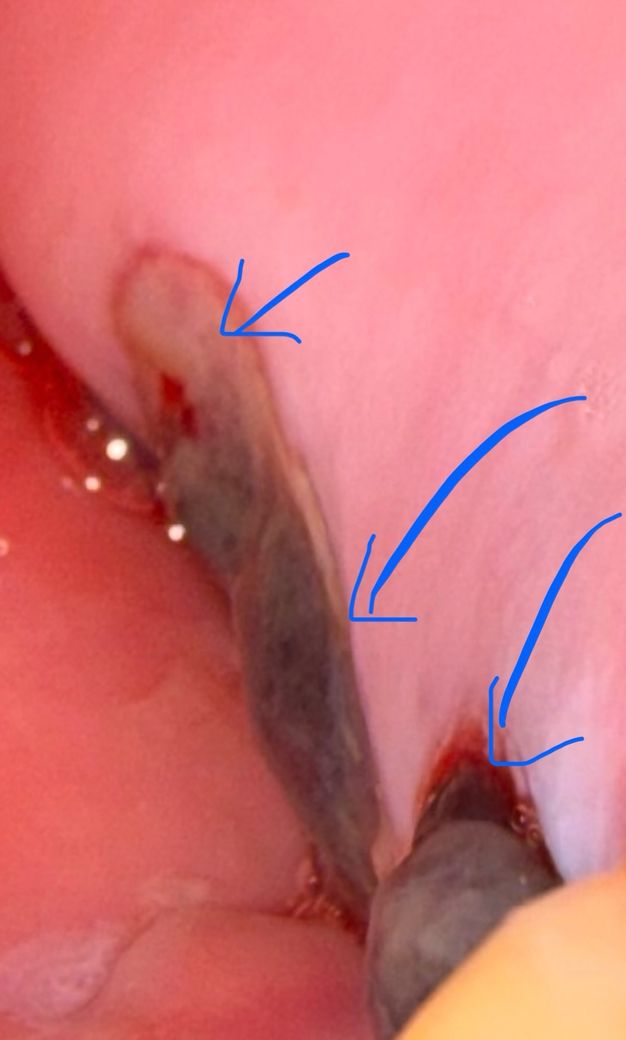

임플란트 3일째 입니다. 젤리같은게 있어요

매복 사랑니 발치 하고

치아2개 발치후 픽스2개 당일 식립했는데

다음날 보니 젤리같은 느낌?(혀로 느꼈을때)

앞쪽은 튀어나와 있는데

3일째인데 아직도 있어요

병원 가봐야 하나요???

정확한 것은 알 수 없으나 뼈이식 재료 일가능성이 높습니다. 병원을 가실 필요는 없습니다.

잇몸이 치유되면서 생기는 자연스러운 현상이니 자극하지 마시고 시간이 지나면 괜찮아 집니다.

잇몸 수술을 하거나 해서 잇몸에 상처가 있는 경우 해당 부위에 혈병이 형성되게 됩니다. 혈병은 딱지와 같은 것인데 잇몸이 아무는 데 도움이 되기 때문에 혈병을 제거하지 않도록 하는 것이 좋습니다.